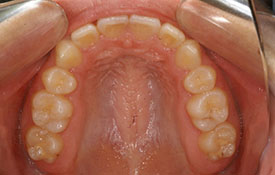

インビザラインの治療例:CASE-1

| プロフィール | 42歳 女性 |

| 所見 | 他院で行われた矯正歯科治療後の後戻りに悩まれて来院されました。 アイライナーの装着は、1日平均20時間ほどでした。 |